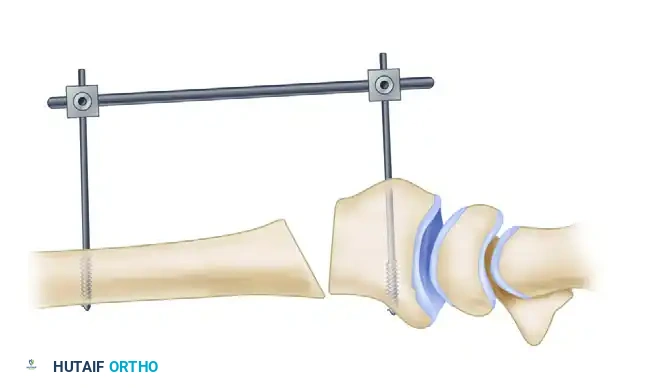

3. Application of the External Fixator

To maintain the corrected alignment and provide stability during graft insertion and plate application, utilize a small external fixator frame. Place one pin in the radial diaphysis and another in the distal fragment (or the metacarpals, depending on the frame design). This acts as a temporary distraction device.

4. Executing the Osteotomy

Using a fine sagittal saw under continuous saline irrigation to prevent thermal necrosis, create the osteotomy at the planned site (preferably the original fracture line).

Once the cortex is breached, insert a small lamina spreader clamp into the osteotomy gap. Gently and progressively wedge the osteotomy open.

Crucial Step: Preserve the dorsal periosteum whenever possible. An intact dorsal periosteal hinge acts as a tension band, significantly increasing the stability of the construct and providing a vascularized bed for bone healing. A standard opening wedge osteotomy with an intact dorsal hinge can safely correct up to 10 mm of radial shortening.